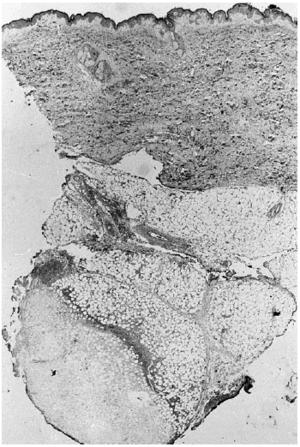

A los pocos días le apareció una lesión nodular dolorososa en el costado, de 6 cm de diámetro, de superficie eritematosa y crecimiento rápido. Se realizó biopsia cutánea, enviando muestra para cultivo y para estudio histopatológico. En el cultivo se identificó Aspergillus flavus y el examen histológico mostraba en piel una lesión centrada en el tejido celular subcutáneo (fig. 1) donde se observaba un área de necrosis amplia de los lobulillos adiposos (figs. 2 y 3), en cuyo interior se reconocían abundantes nidos de hifas fúngicas tabicadas, positivas con las tinciones de PAS y metenamina plata.

Fig. 2.--Área de necrosis del tejido adiposo donde se observan en la zona periférica hifas de Aspergillus.